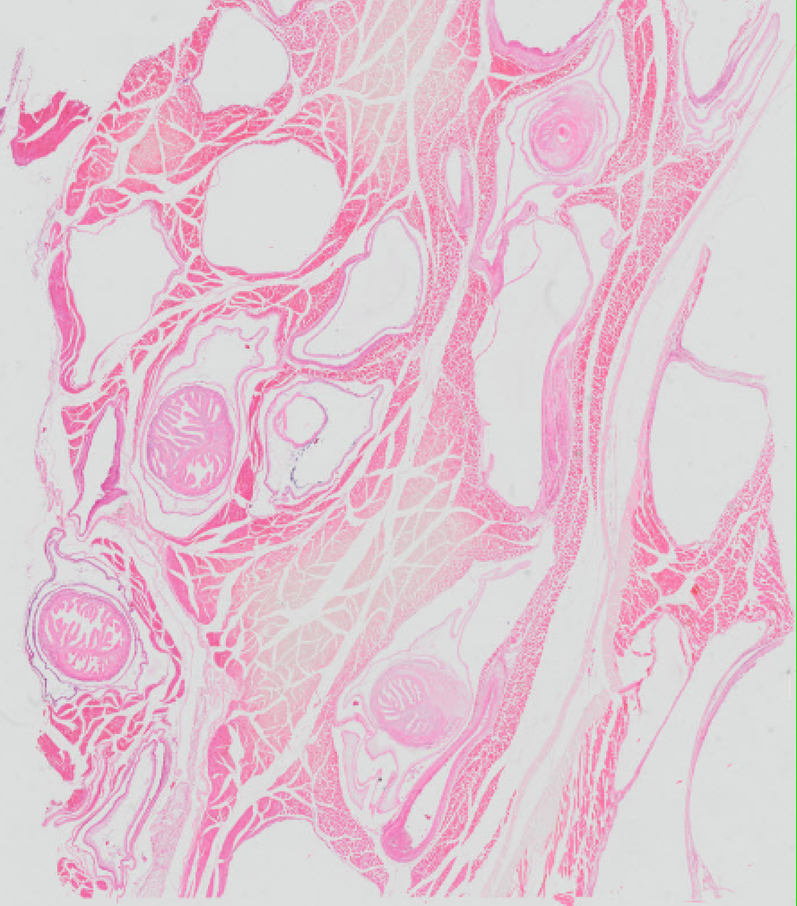

Echinococcus multilocularis - Tasiemiec wielojamowy - Torbiel z protoskoleksami